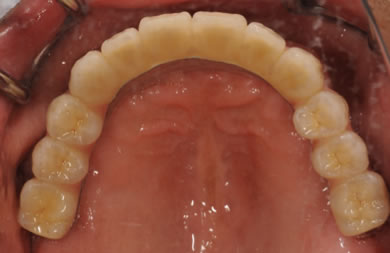

インプラントの症例写真 IMPLANT

骨再生スピードインプラント治療+AGC連結セラミック治療+セラミック治療

| 治療方針 | ソケットリフト法により上顎洞底部を拳上することにより、骨の無い部分に骨をつくってあげ、インプラント治療を可能にする。さらに歯周病により組織の破壊が著しいので、AGC連結セラミック治療により上顎の審美的回復を行う。 | ||||||||||||||||||||||||||||||||

| 治療内容 | インプラント7本(抜歯AGC即日スピードインプラント+ソケットリフト)、AGCハイブリッドセラミック連結ブリッジ1装置(上顎)ハイブリッドセラミック8本 | ||||||||||||||||||||||||||||||||